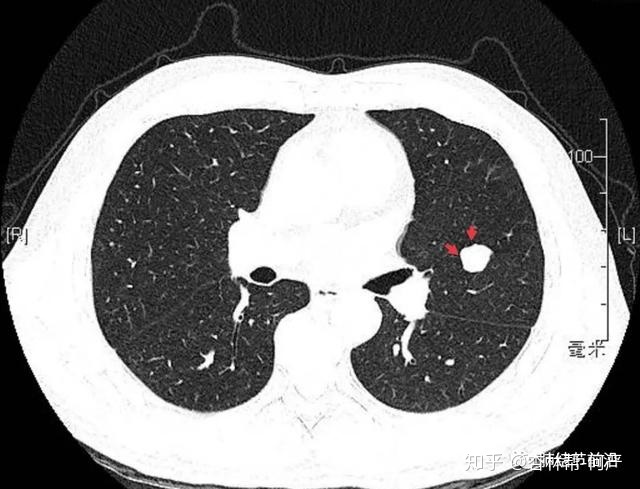

肺结节是指肺内直径小于或等于3cm的类圆形或不规则形病灶,影像学表现为密度增高的阴影,边界清晰或不清晰的病灶。